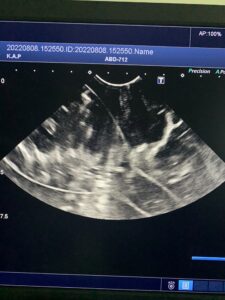

下の写真に写っているエコー検査画像は、水の中に浮かんだ「あるもの」を2つの断面で見たものです。さて、「あるもの」とはなんでしょう?

※臓器ではありません。身近にある日用品(?)です。